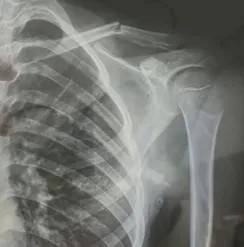

10月30日,内蒙古自治区赤峰市宁城县苏木皋小学一学生家长贾女士给记者打来电话,介绍了孩子被打的原因虚拟币app源代码。贾女士称,放学通道的墙上有一个电灯的开关,好多孩子放学时都随手去拨弄开关。出于安全考虑,学校和老师都禁止孩子拨弄开关。23日放学时,他儿子和另一个同学调皮,再去拨弄了那个开关,被正在值班的另一个班的班主任发现,把她儿子打了,且打骨折了。

图片由报料者提供